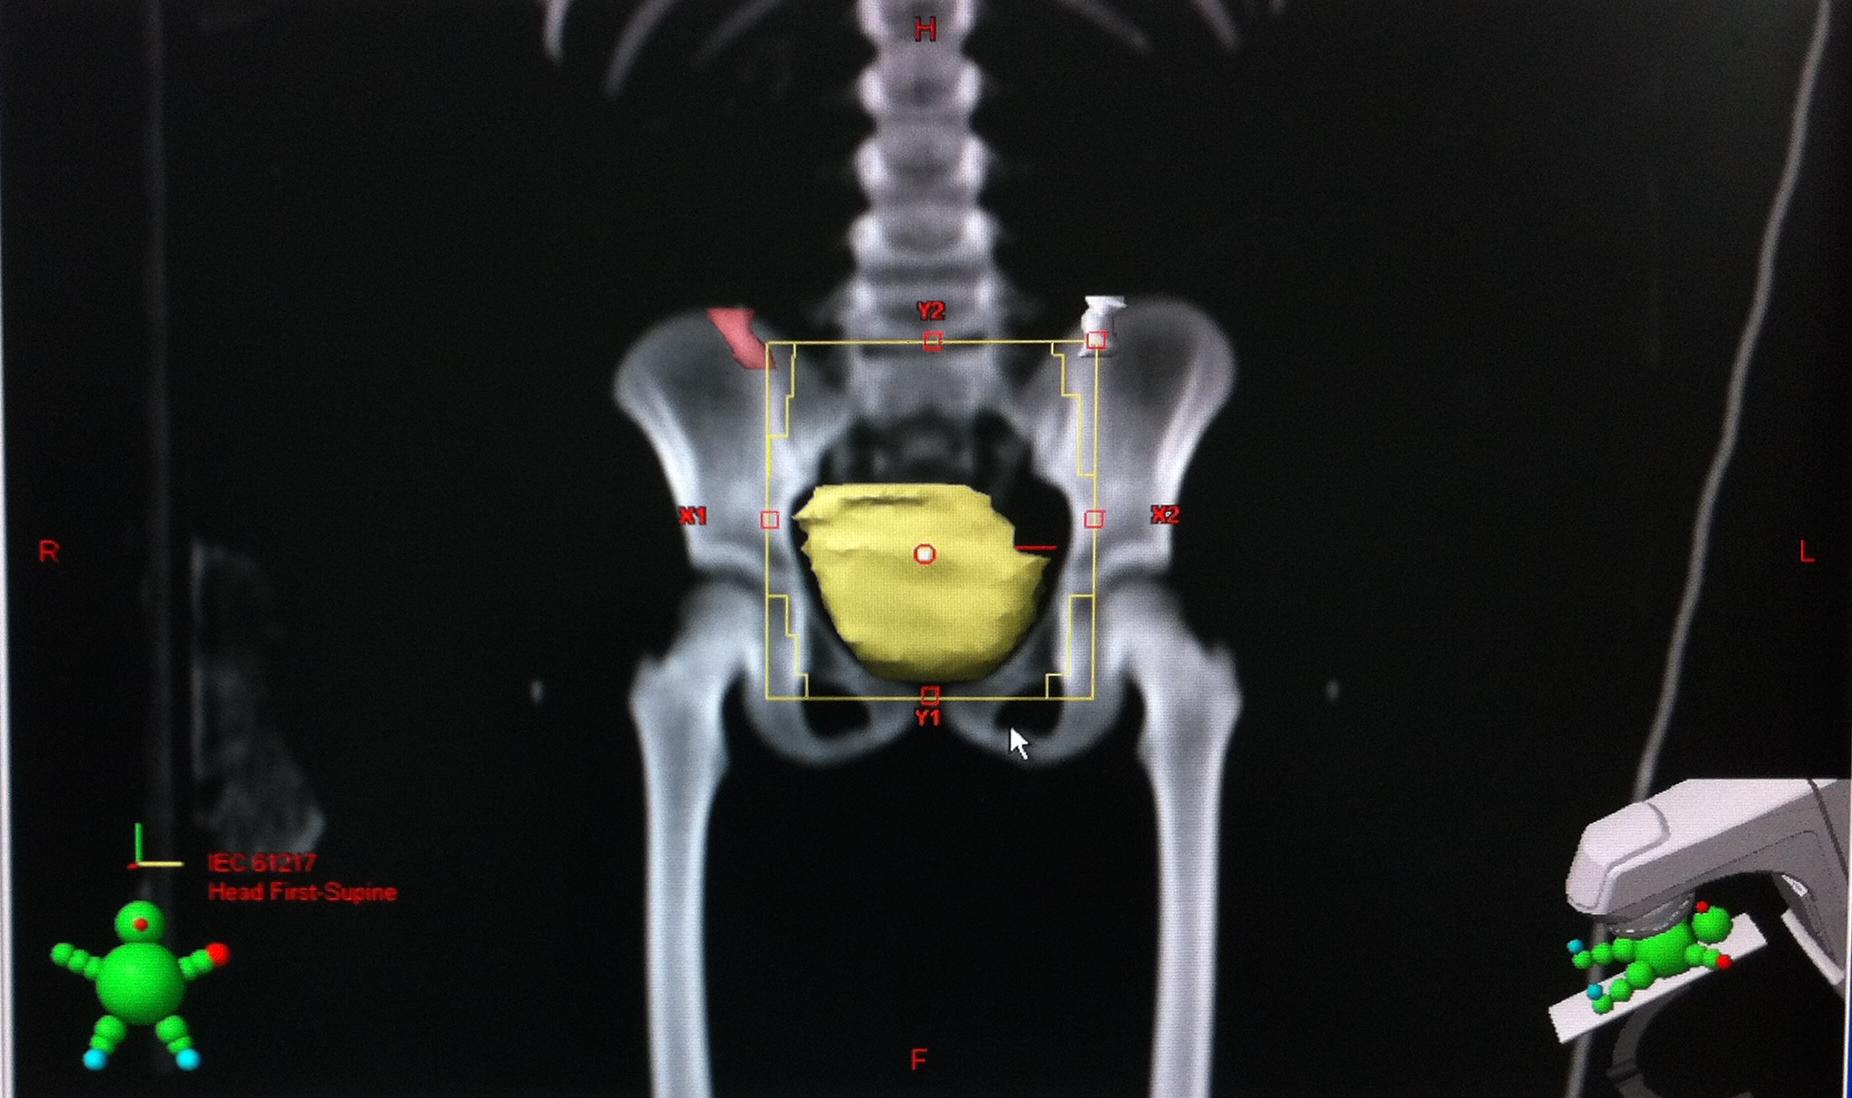

After the first medical consultation 2.2% of children aged less or equal 5 years were cooperating for the treatment. In 93 cases, we brought the children a week before the scanner simulation to familiarize them to technical platform team including manipulators, radiotherapist and to explain the contention with masks if necessary and how to make the sessions radiotherapy. We used aesthesia for the all sessions of radiotherapy in 28 cases. Until 2008 all patient were treated by 2 D radiotherapy with Cobalt 60 machine (Figure 1) and after we used conformational 3D radiation therapy by 2 linear accelerators during all the day especially during the morning. All children, had system contention to minimize the shifting (Figures 2 and 3). Five girls had ovarian transposition, 2 for medulloblastomas and 3 for pelvic rhabdomyosarcomas (Figure 4). Regarding the stage of the tumor at the diagnosis, 75% of patients had a locally advanced stages and the median time to start was more than 1 month in 68% and 12% more than 3 months.

![]() |

Figure 4: delineation of the organ at risk left ovary (white), right ovary (red) after transposition and bladder (yellow) |